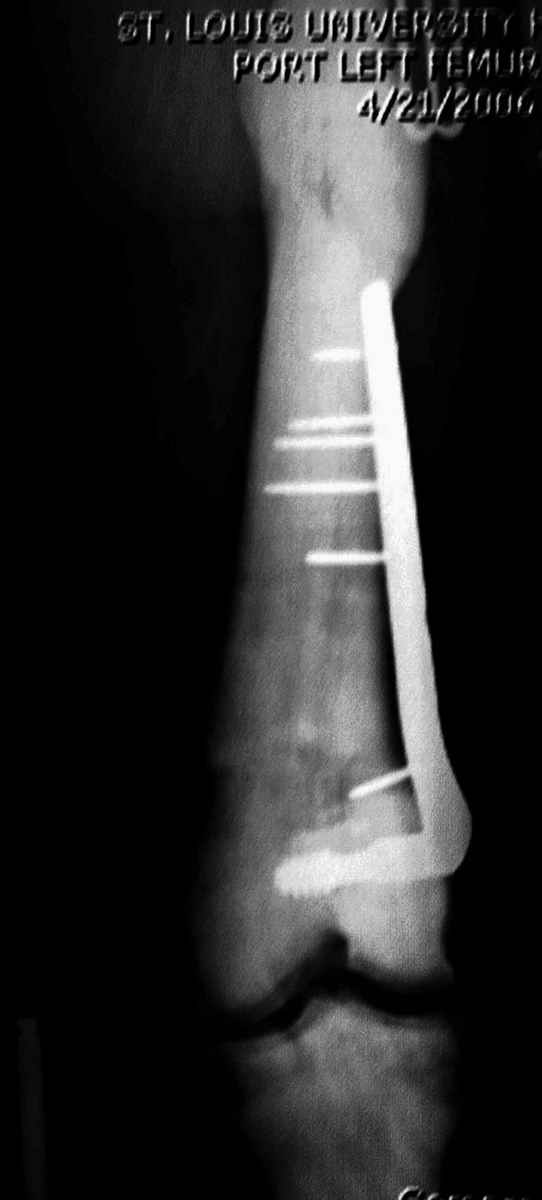

“При лечении переломов у больных с остеопетрозом (в прошлом году был случай) необходимо быть готовым к длительным операциям из-за трудности

обработки традиционными методами "мраморной" кости, иметь в наличие достаточное количество свежих острых инстументов и персонала при необходимости замены (были случаи отстрочки операции на следующий день из-за физической усталости персонала), и надо избежать особо трудоемких операции как интрамедуллярное сверление”.

слайды из прошлегодного случая.

Djoldas Kuldjanov, MD

Department of Orthopedic Surgery

St. Louis University Medical Center